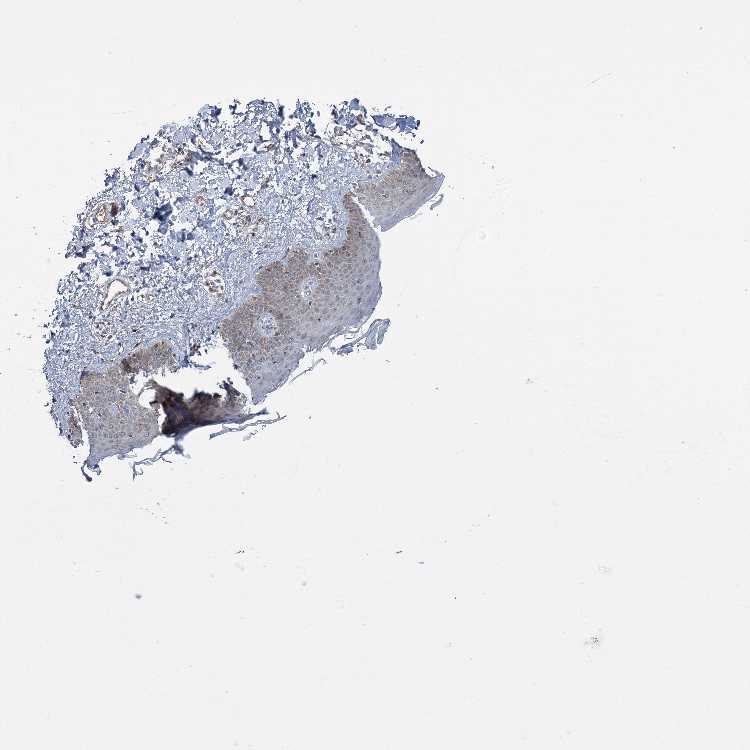

SKIN 1 - Antibody stainingi

Antibody staining in the annotated cell types in the current human tissue is reported as not detected, low, medium, or high, based on conventional immunohistochemistry profiling in selected tissues. This score is based on the combination of the staining intensity and fraction of stained cells.

Each image is clickable and will lead to virtual microscopy that enables deeper exploration of all samples and also displays staining intensity scores, fraction scores and subcellular localization as well as patient and tissue information for each sample.

Antibody HPA038021

Langerhans Medium

Fibroblasts Medium

Keratinocytes Low

Melanocytes Medium